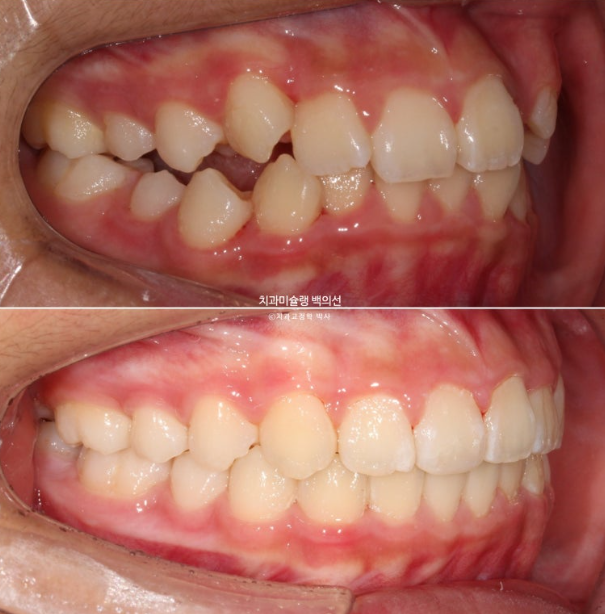

이제 전 후 비교해 보겠습니다.

총 치료기간은 1년 6개월이고 중간에 중심선 이슈로 잠시 쉬는 시간이 4개월 있었습니다.

재제작은 총 2회 했습니다.

24.02~25.07

치료결과가 어린이 교정이 아닌 정식 성인교정 치료 결과에 준한만큼 유지장치도 철저히 들어갑니다.

어긋난 중심선이 맞아졌으며 기울어진 앞니 치축도 좋아졌습니다.

앞니가 깊게 물리는 과개교합도 좋아졌습니다.